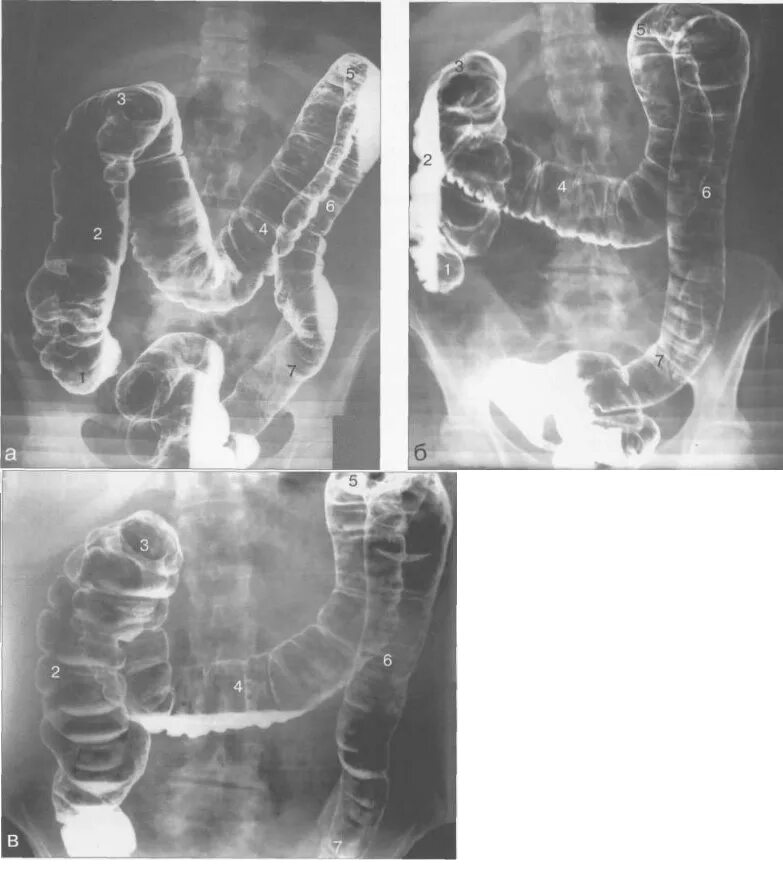

Ирригоскопия с двойным контрастированием